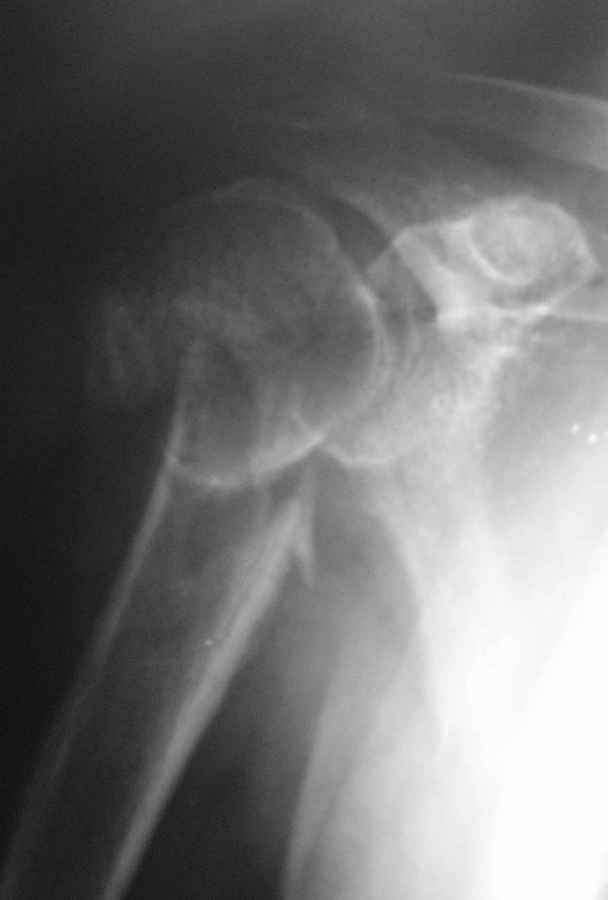

Пациент 55 лет. травма 7.07.09г (первая Р-грамма). Лечился консервативно, надолго выпадал из под наблюдения леч. врача. Последний снимок от 7.08.09 г. Как видно на Р-грамме, стояние отломков неудовлетворительное, клинически выраженная патологическая подвижность. Соп. дз: сахарный диабет 1 типа, средней тяжести.